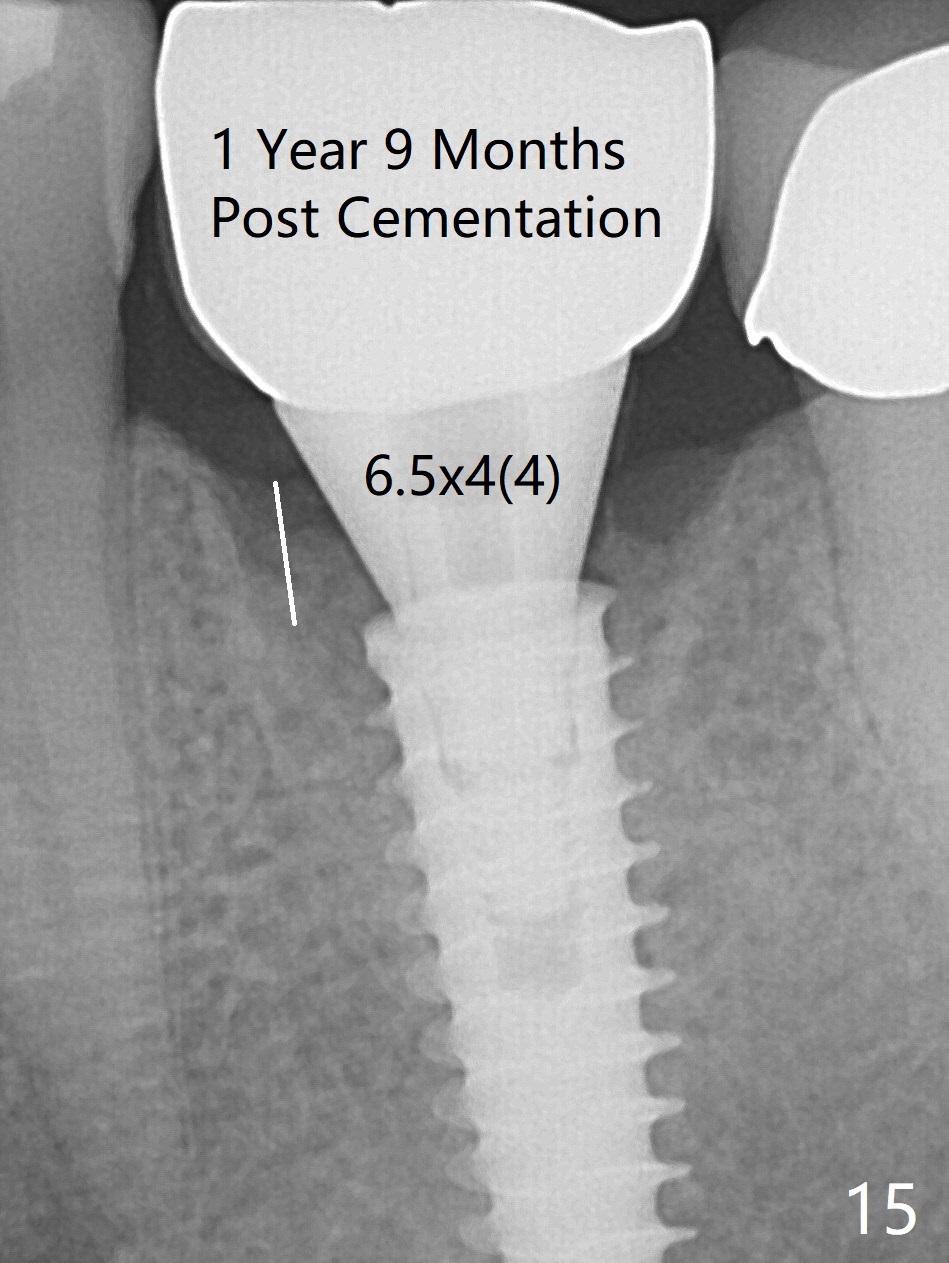

The gingiva looks healthy 8 months postop (3 months post cementation (after abutment screw retightening and addition of porcelain to proximal surfaces, Fig.12).  New bone has apparently covered the implant plateau (Fig.13 arrows). Bone density between threads increases 9 months post cementation (Fig.14).  There is 2 mm bone superior to the implant plateau mesial and distal 1 year 9 months post cementation (Fig.15,16).  The crown/abutment is loose 3 times (3 months (Fig.14), 11 months (between Fig.14 and 15) and 2 years 3 months post cementation).  In spite of being stable 3 years 10 months post cementation, a smaller abutment is placed (Fig.17 (PA), 18 (BW)) with impression for a new crown.  After intraoral cementation, the new crown/abutment is removed for residual cement removal.  When the complex is reseated, it is not smooth, probably due to proximal undercut.  Fortunately the abutment appears to be completely seated, followed by 20 Ncm torque (Fig.19).